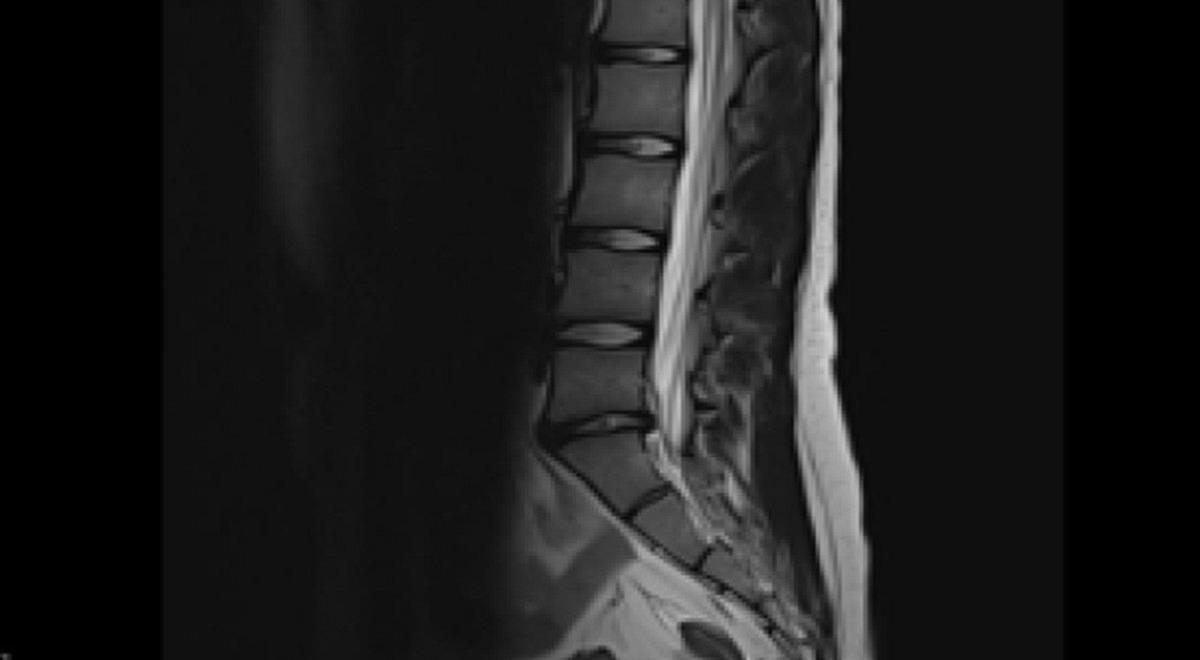

Beeldvorming speelt tegenwoordig een belangrijke rol in de diagnostiek bij klachten van het steun- en bewegingsapparaat en de mogelijkheden zijn groot. Er zijn verschillende technieken voorhanden, waaronder conventionele röntgenfoto’s, CT-scans, echografie en MRI-scans. Verschillende aanvullende beeldvormingstechnieken hebben specifieke voor- en nadelen die samenhangen met de achterliggende techniek. Dit artikel bespreekt hoe deze beeldvorming technisch tot stand komt, wanneer aanvullende beeldvorming geïndiceerd is bij veelvoorkomende klachten van de rug, knie en enkel, en welke informatie daarmee wordt vergaard.